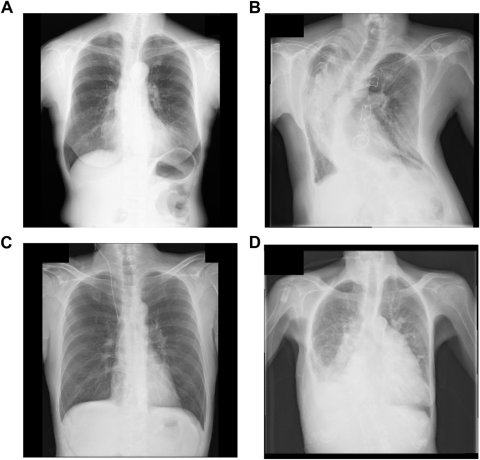

This is further complicated by images with various rotations. A radiograph be taken from the anterior to the posterior or vice versa, and it can also be lateral, inverted or rotated, further complicating the dataset. In large imaging archives, these minor errors quickly add up to hundreds or thousands of mislabeled results.

A research team at Osaka Metropolitan University Graduate School of Medicine, including graduate student Yasuhito Mitsuyama and Professor Daiju Ueda, aimed to improve the detection of mislabeled data by automatically identifying errors before they affect the input data for deep-learning models. The group developed two models: Xp-Bodypart-Checker, which classifies radiographs depending on the body part; and CXp-Projection-Rotation-Checker, which detects the projection and rotation of chest radiographs.